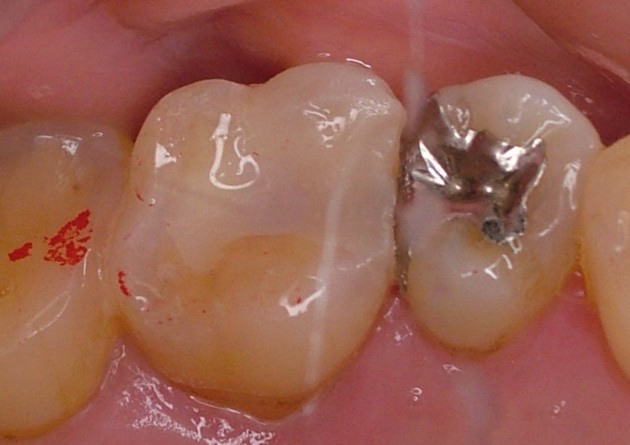

光重合レジンによる再充填